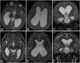

Transependymal CSF flow

Normal-pressure hydrocephalus (NPH), also called malresorptive hydrocephalus, is form of communicating hydrocephalus in which excess cerebrospinal fluid (CSF) occurs in the ventricles, and with normal or slightly elevated cerebrospinal fluid pressure. As the fluid builds up, it causes the ventricles to enlarge and the pressure inside the head to increase, compressing surrounding brain tissue and leading to neurological complications. [Source: Wikipedia ]